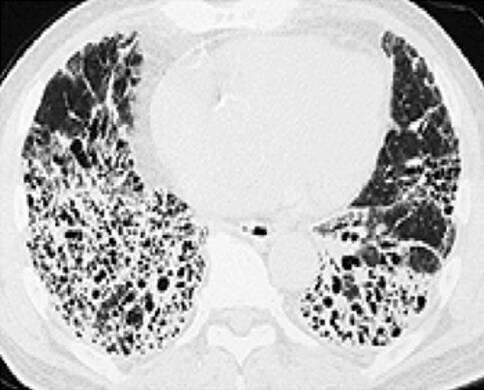

特发性肺纤维化(IPF)是一种致死率很高的呼吸系统疾病,是特发性间质性肺炎常见的一种类型,其特征为弥漫性肺泡炎和肺泡结构紊乱所致的肺间质纤维化。IPF主要表现为进行性加重的呼吸困难,伴限制性通气功能障碍和气体交换障碍,可致低氧血症、甚至呼吸衰竭。目前发病机制还不明确,且缺乏有效的治疗方法。那么现在针对特发性肺纤维化究竟有哪些治疗方法呢?本文中,小编总结了目前治疗特发性肺纤维化的常见方法,希望能为大家提供一些参考。

图源:日本呼吸器学会